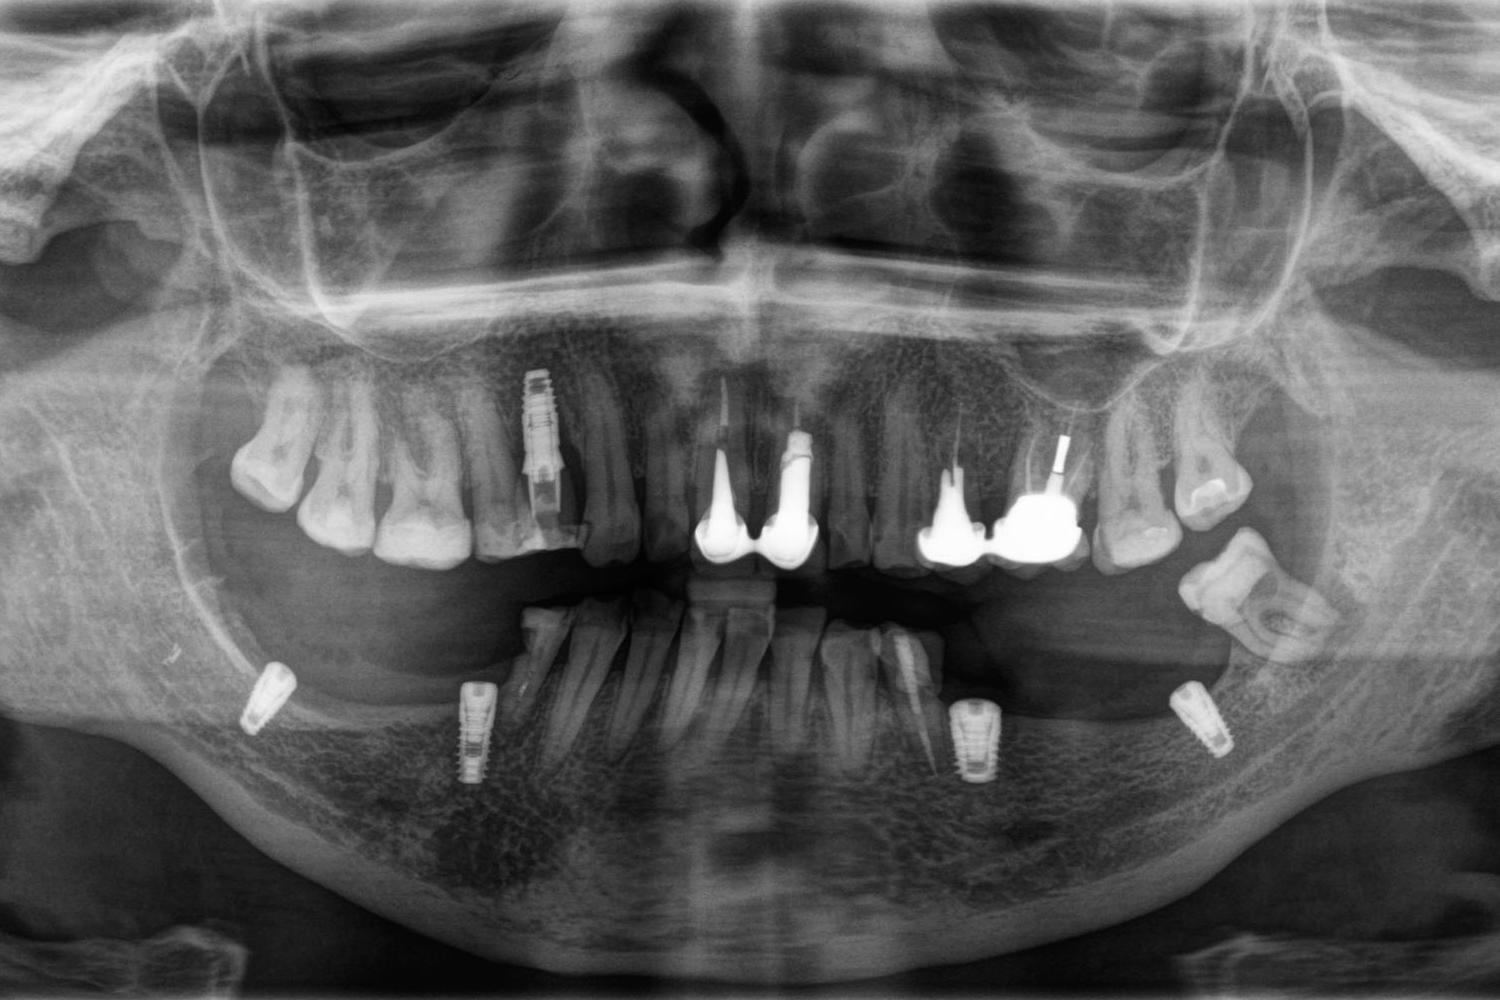

На КТ-исследовании мы обнаружили уменьшение объема кости и то, что в дальних отделах нижней челюсти расстояние до нижнечелюстного нерва составляет 5-6 мм. Поскольку была задача провести имплантацию и протезирование с минимальными финансовыми затратами, было принято решение сделать функциональную работу (без костной пластики).

Сложность работы заключалась в том, что нужно было расположить имплантат таким образом, чтобы он проходил по передней стенке нижнечелюстного нерва, не задев его. Такую работу можно сделать только с помощью специального КТ-аппарата и специализированных программ. После планирования имплантации и изготовления шаблона мы смогли установить импланты так, как мы хотели (не задев нерв) и получили прогнозируемо хороший результат.